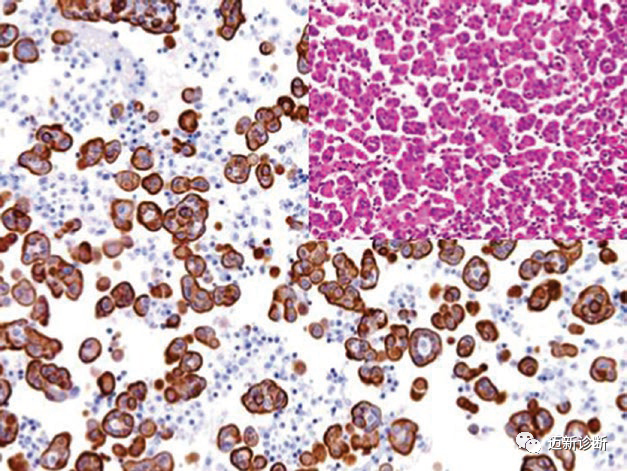

In immunohistochemical detection, CK generally shows diffuse cytoplasmic staining, but there are other staining patterns, such as perinuclear and dot-like expression in neuroendocrine tumors. Common tumor types exhibiting this staining pattern also include: Merkel cell carcinoma (perinuclear staining, mainly CK20), small cell carcinoma (mainly CK19), carcinoid and pancreatic endocrine tumors, renal oncocytoma (low molecular weight CK), medullary thyroid carcinoma, seminoma (low molecular weight CK), granular cell tumor, rhabdomyomatous tumors, and a few stromal tumors (such as desmoplastic small round cell tumor, leiomyosarcoma, monophasic synovial sarcoma).

Figure 1. In diffuse gastric adenocarcinoma, tumor cells diffusely express broad-spectrum CK (MNF116).